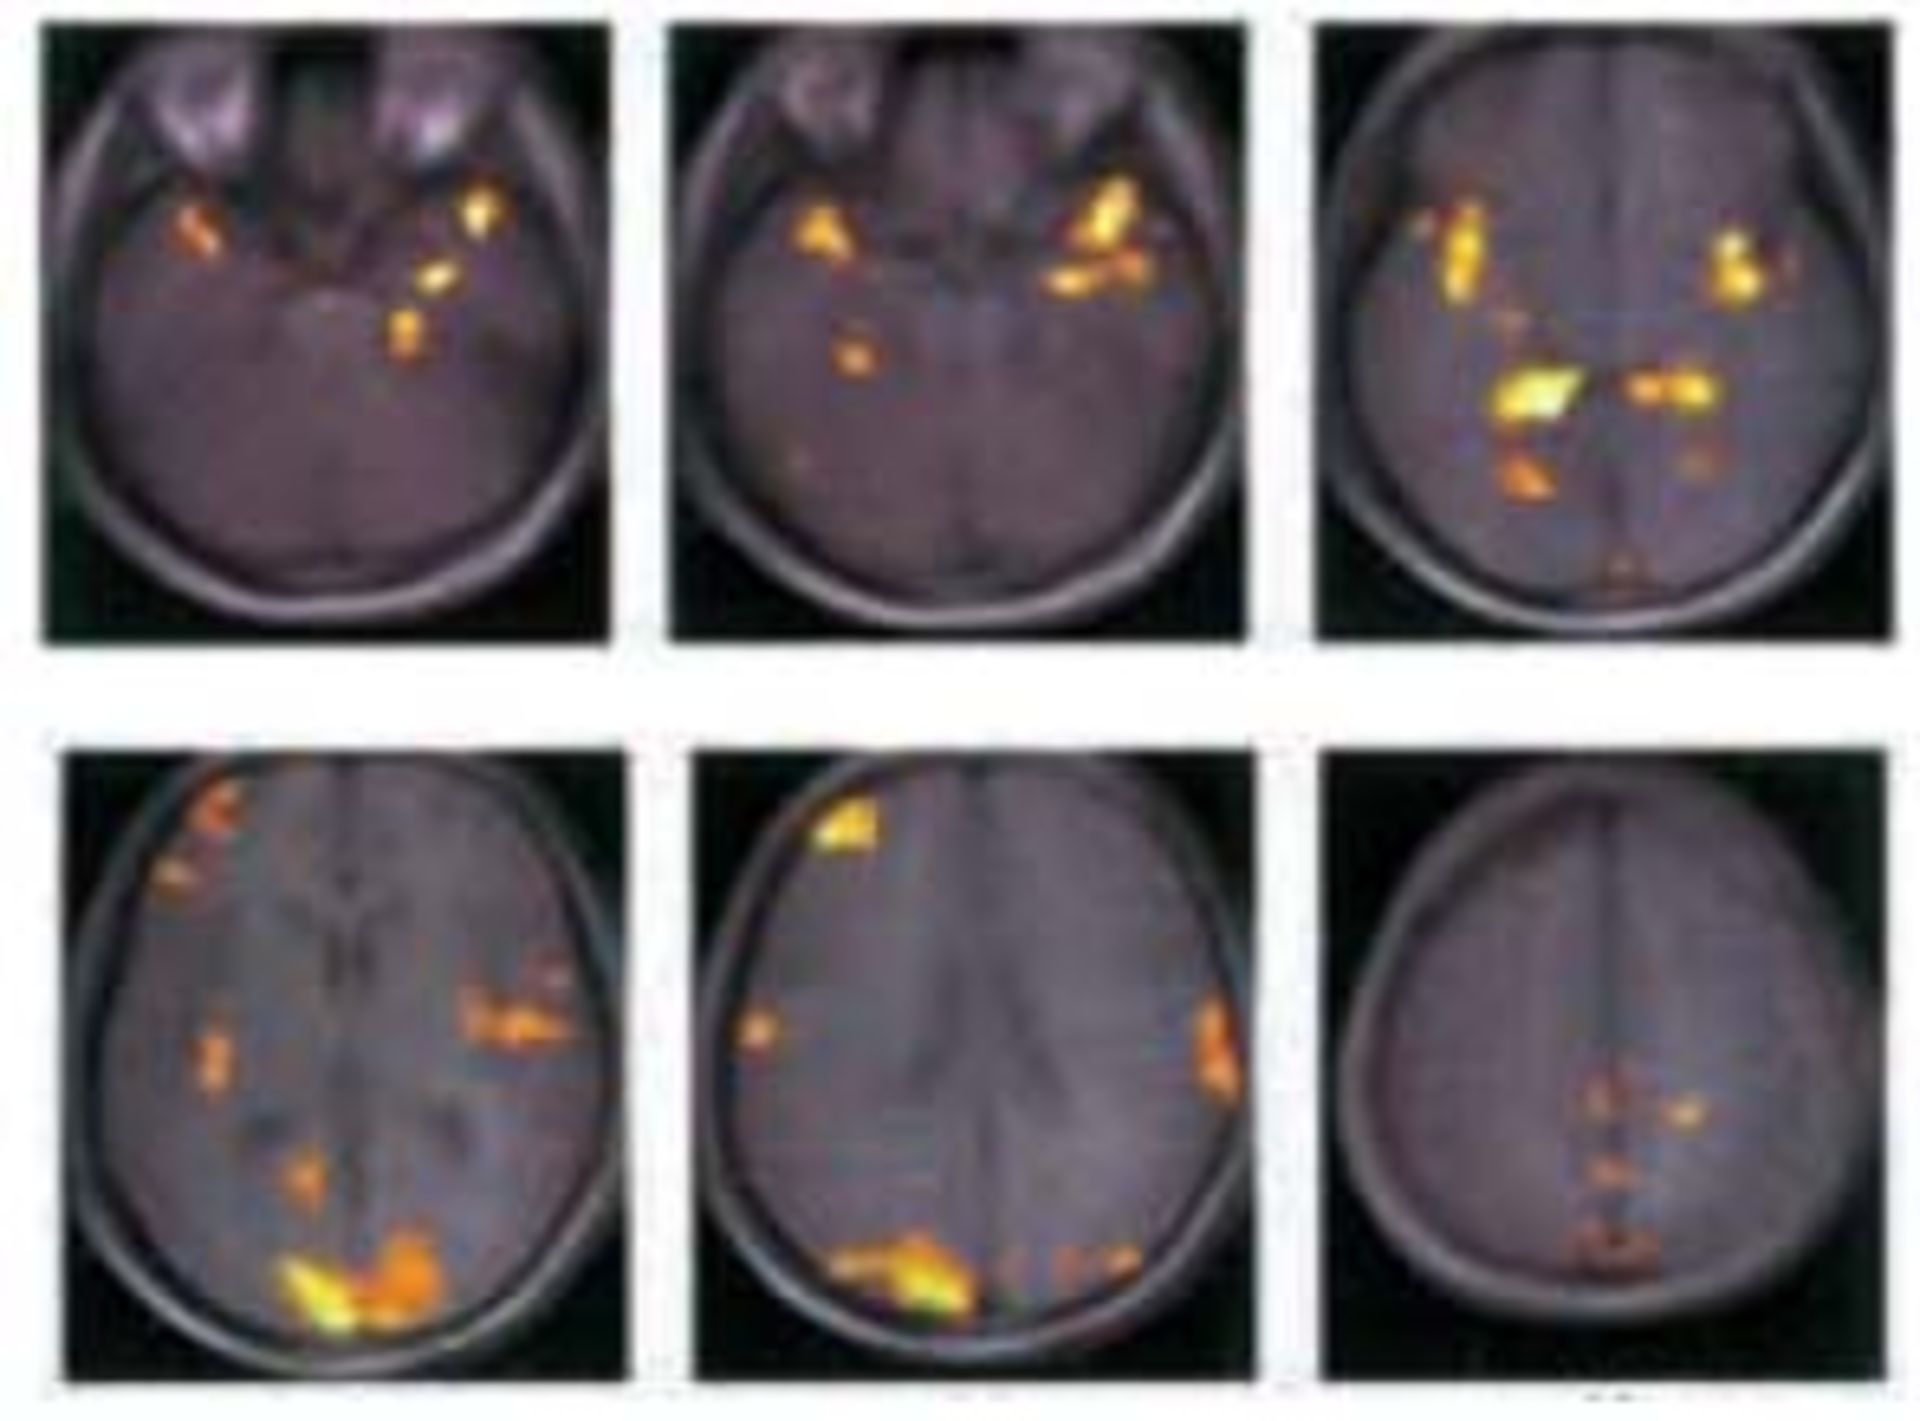

در واقع در حالی که تصور می‌شود مغز ما در حالت رویاپردازی عملکرد چندانی ندارد و در حالت استراحت است ولی تحقیقات نشان می‌دهند که در این گونه موارد فعالیت در بسیاری از مناطق مغز افزایش می‌یابد. تصویری که در ادامه با هم می‌بینیم اسکن مغز فردی است که در حال رویاپردازی است.

daydreaming

برخی تحقیقات نشان می‌دهند که مغز ما برخی از سخت‌ترین مسائلی را که با آنها روبرو است، در حالت خیال‌بافی و استراحت حل می‌کند چیزی که شاید شما هم  هنگامی که در موقع رانندگی غرق در افکار خود بوده‌اید یا در هنگام حمام کردن آن را تجربه کرده باشید. این راه حل‌ها که که معولا به یکباره به ذهن ما می‌رسند محصول اندیشیدن در حالت غیر متمرکز هستند.